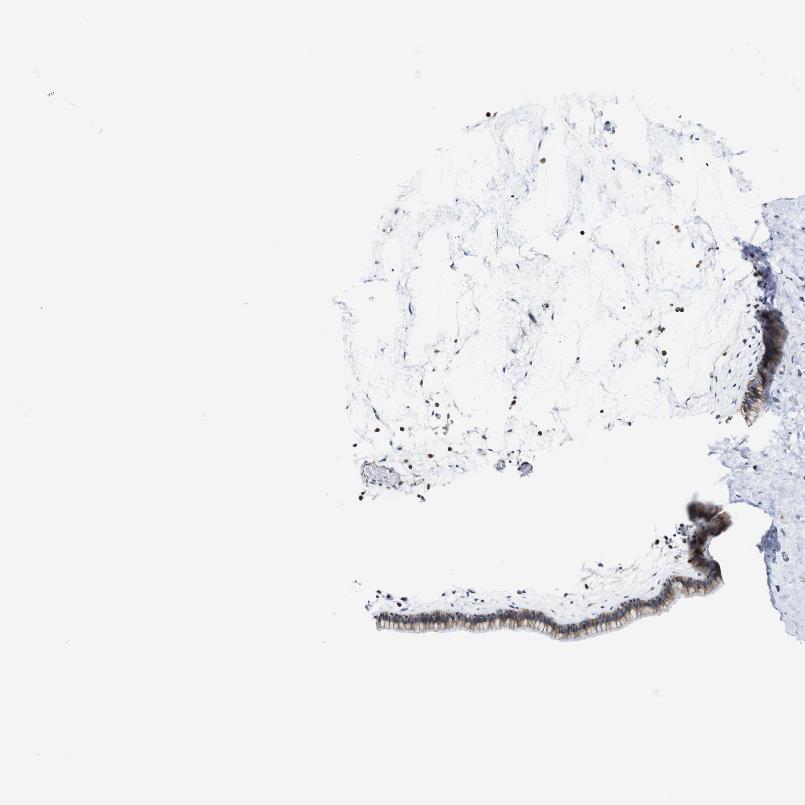

TISSUE PRIMARY DATA NASOPHARYNX Show tissue menu

NASOPHARYNX - Antibody stainingi

Antibody staining in the annotated cell types in the current human tissue is reported as not detected, low, medium, or high, based on conventional immunohistochemistry profiling in selected tissues. This score is based on the combination of the staining intensity and fraction of stained cells.

Each image is clickable and will lead to virtual microscopy that enables deeper exploration of all samples and also displays staining intensity scores, fraction scores and subcellular localization as well as patient and tissue information for each sample.

Antibody HPA013373

Respiratory epithelial cells Medium